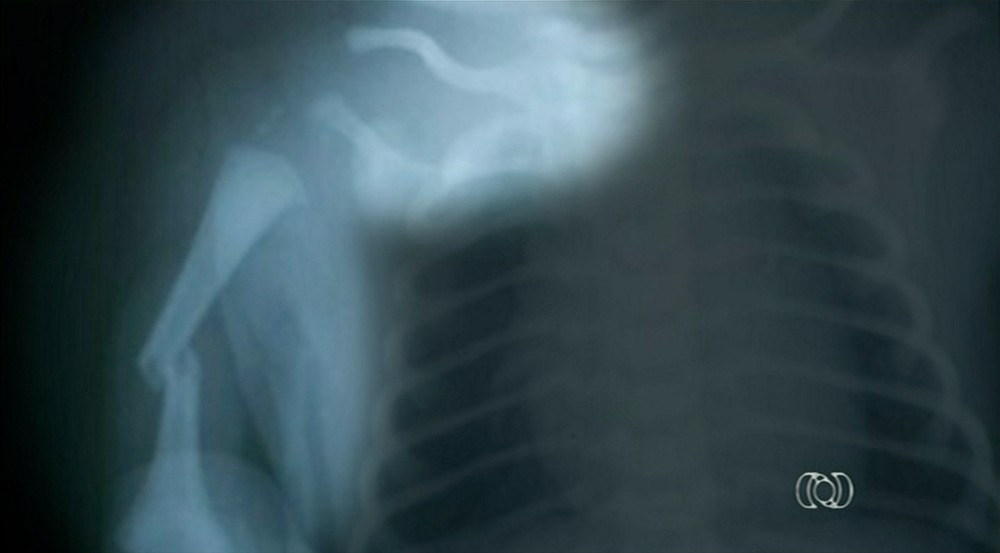

Um bebê teve um braço e a clavícula quebrados durante o parto em uma maternidade, em Palmas.

O bebê nasceu com 4,6 kg e complicações, e a mãe ainda está internada na maternidade.